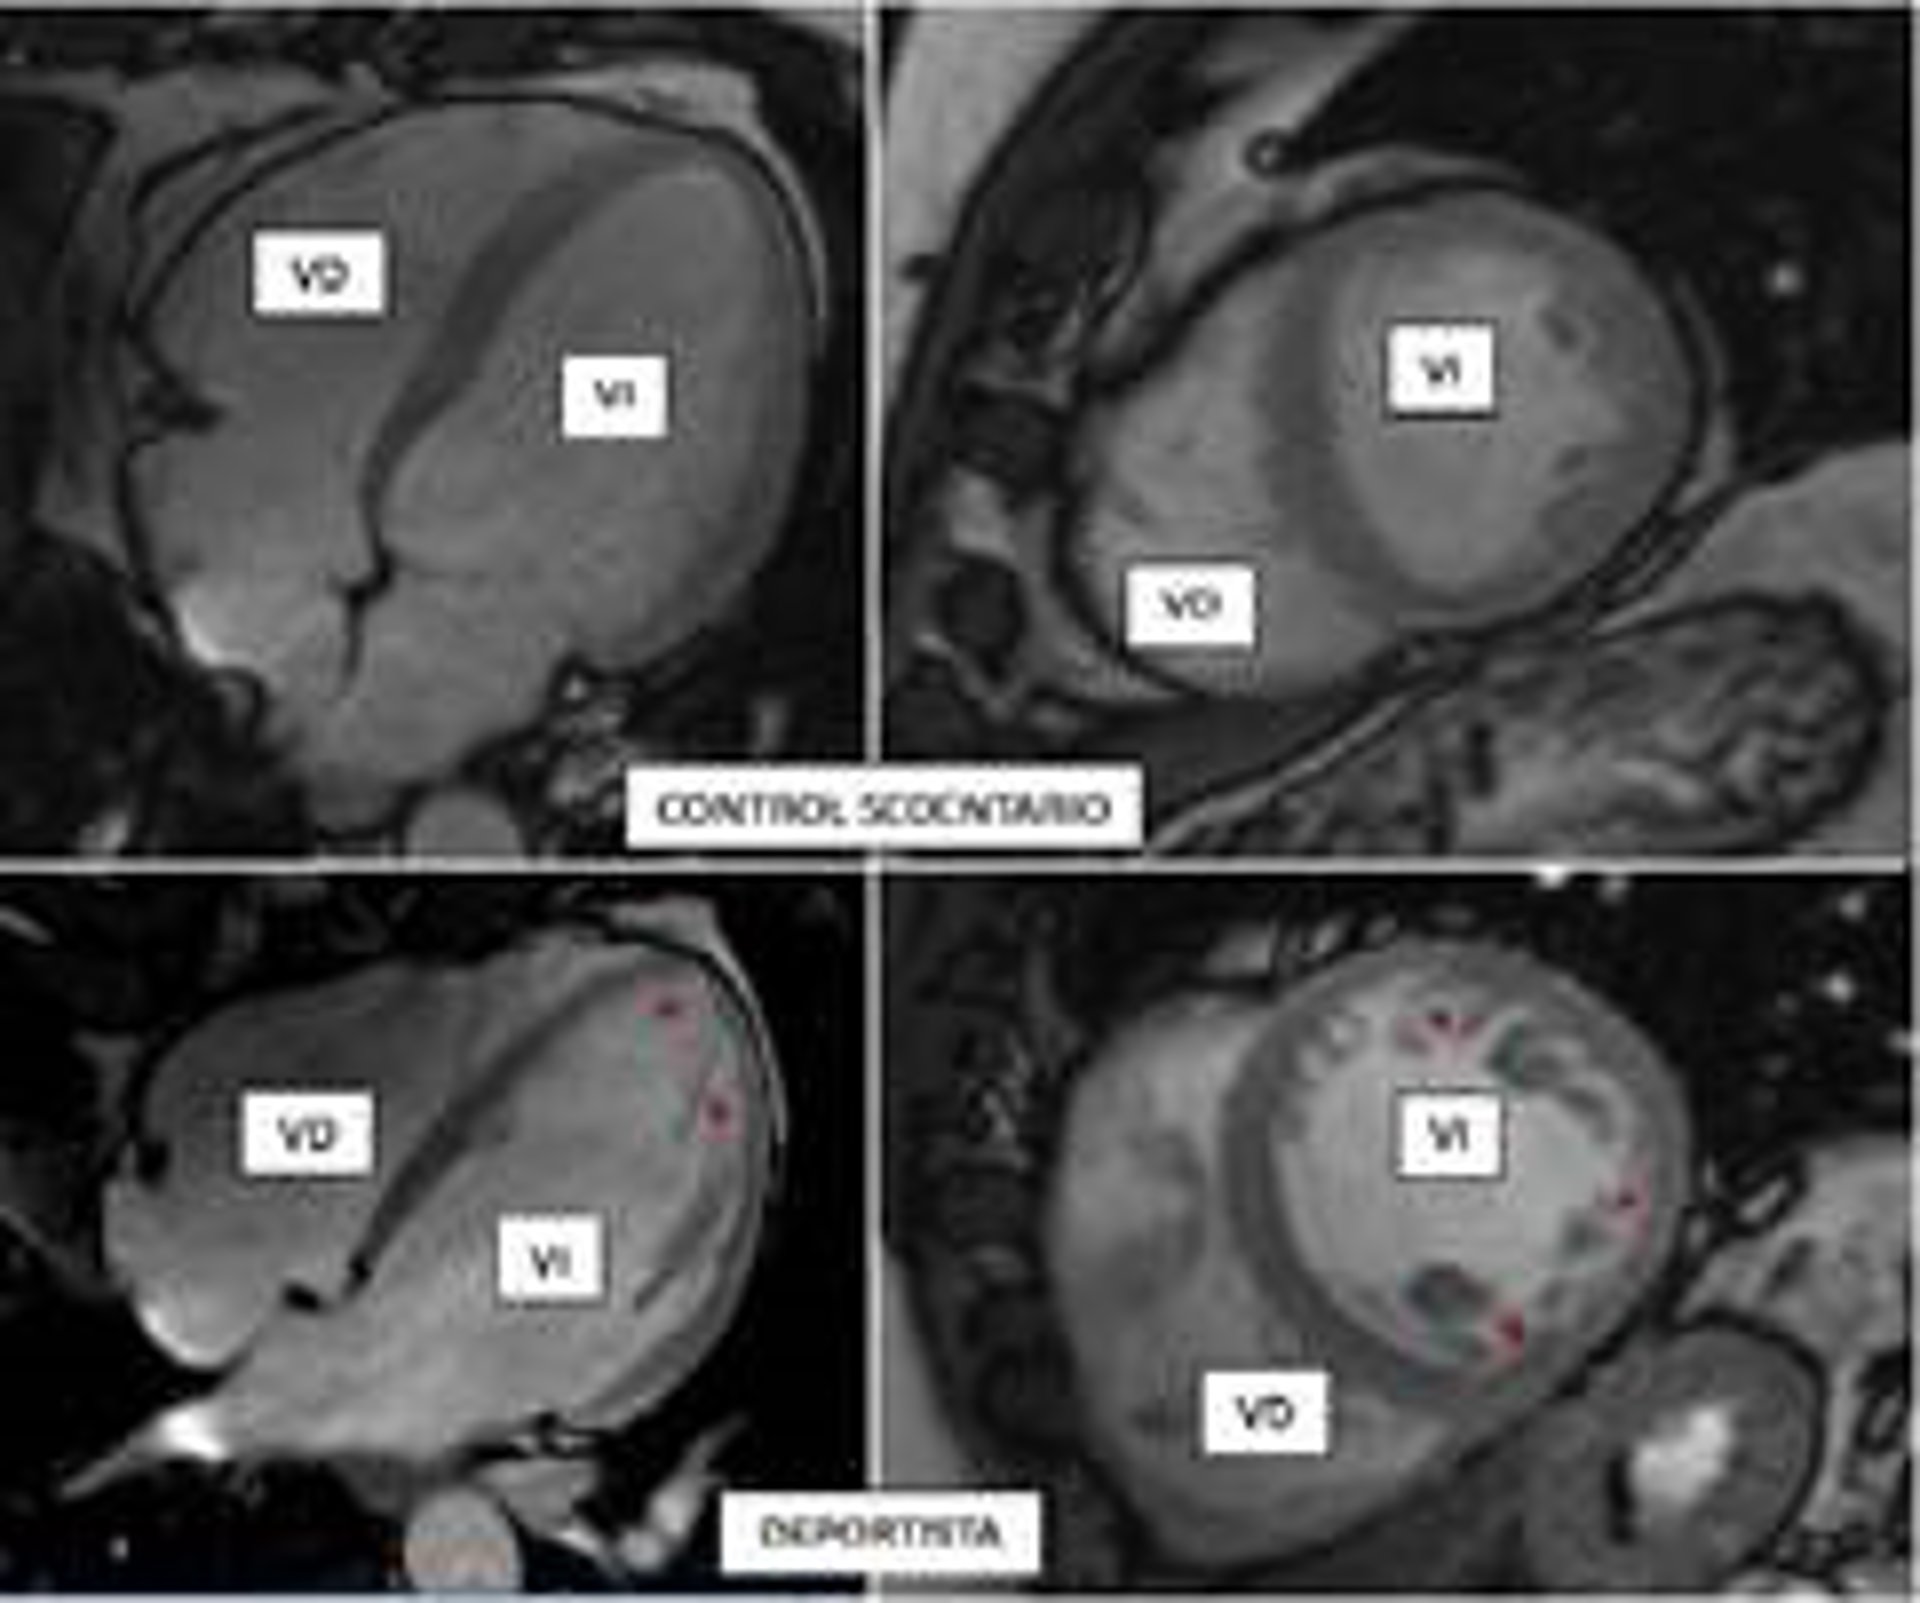

La Figura Muestra Imágenes Mediante Resonancia Magnética De Los Corazones De Un Participante Control (Fila Superior) Comparado Con Un Deportista Vigoroso (Fila Inferior).

La Figura Muestra Imágenes Mediante Resonancia Magnética De Los Corazones De Un Participante Control (Fila Superior) Comparado Con Un Deportista Vigoroso (Fila Inferior). - CNIC